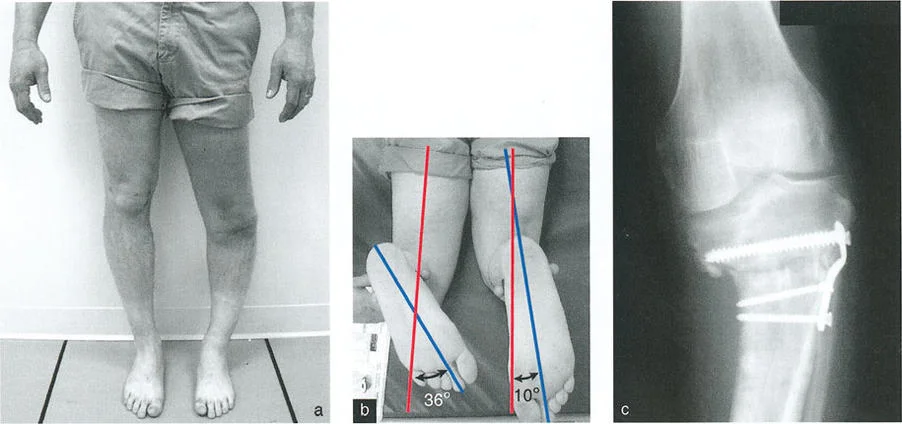

- فحص الدوران المحوري للأطراف (على سبيل المثال، محور الفخذ-القدم لدوران الساق).

- الأشعة السينية الأمامية الخلفية والجانبية (AP and Lateral Radiographs): تُستخدم لتقييم التشوه في المستويين التاجي (التقوس للداخل أو الخارج) والسهمي (التقوس للأمام أو الخلف).

- التصوير المقطعي المحوسب (CT Scan): يُعد حاسمًا لتقييم التشوهات الدورانية (الالتواء) التي لا تظهر بوضوح في الأشعة السينية التقليدية، ولإجراء قياسات ثلاثية الأبعاد دقيقة للعظم.